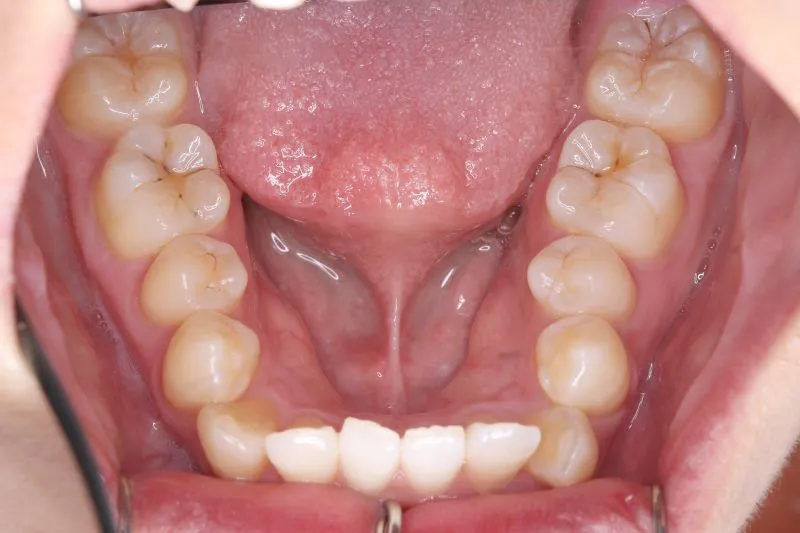

治療経過1

治療回数42回、3年1ヶ月の治療期間で矯正治療を終了しました。